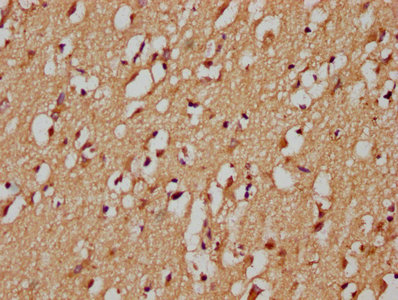

• IHC image of CSB-PA856909LA01HU diluted at 1:200 and staining in paraffin-embedded human brain tissue performed on a Leica BondTM system. After dewaxing and hydration, antigen retrieval was mediated by high pressure in a citrate buffer (pH 6.0). Section was blocked with 10% normal goat serum 30min at RT. Then primary antibody (1% BSA) was incubated at 4°C overnight. The primary is detected by a biotinylated secondary antibody and visualized using an HRP conjugated SP system.